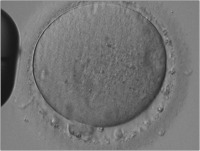

Die Bedeutung der Morphologie der Oozyte hinsichtlich ihres weiteren Entwicklungspotentials

Journal für Reproduktionsmedizin und Endokrinologie - Journal of Reproductive Medicine and Endocrinology 2006; 3 (1): 17-23 Volltext (PDF) Summary Abbildungen